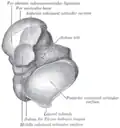

Subtalar joint, viewed from an angle between lateral and frontal.

Though irregular in shape, the talus can be subdivided into three parts.

Facing anteriorly, the head carries the articulate surface of the navicular bone, and the neck, the roughened area between the body and the head, has small vascular channels.[3]

The body features several prominent articulate surfaces: On its superior side is the trochlea tali, which is semi-cylindrical,[6] and it is flanked by the articulate facets for the two malleoli.[3] The ankle mortise, the fork-like structure of the malleoli, holds these three articulate surfaces in a steady grip, which guarantees the stability of the ankle joint. However, because the trochlea is wider in front than at the back (approximately 5–6 mm) the stability in the joint vary with the position of the foot: with the foot dorsiflexed (toes pulled upward) the ligaments of the joint are kept stretched, which guarantees the stability of the joint; but with the foot plantarflexed (as when standing on the toes) the narrower width of the trochlea causes the stability to decrease.[7] Behind the trochlea is a posterior process with a medial and a lateral tubercle separated by a groove for the tendon of the flexor hallucis longus. Exceptionally, the lateral of these tubercles forms an independent bone called os trigonum or accessory talus; it may represent the tarsale proximale intermedium. On the bone's inferior side, three articular surfaces serve for the articulation with the calcaneus, and several variously developed articular surfaces exist for the articulation with ligaments.[3]

For descriptive purposes the talus bone is divided into three sections, neck, body, and head.

The head of talus looks forward and medialward; its anterior articular or navicular surface is large, oval, and convex. Its inferior surface has two facets, which are best seen in the fresh condition.[8]

The medial, situated in front of the middle calcaneal facet, is convex, triangular, or semi-oval in shape, and rests on the plantar calcaneonavicular ligament; the lateral, named the anterior calcaneal articular surface, is somewhat flattened, and articulates with the facet on the upper surface of the anterior part of the calcaneus.[8]

Neck

The neck of talus is directed anteromedially, and comprises the constricted portion of the bone between the body and the oval head.[8]

Its upper and medial surfaces are rough, for the attachment of ligaments; its lateral surface is concave and is continuous below with the deep groove for the interosseous talocalcaneal ligament.[8]

Body

The body of the talus comprises most of the volume of the talus bone (ankle bone). It presents with five surfaces; a superior, inferior, medial, lateral and a posterior:[8]